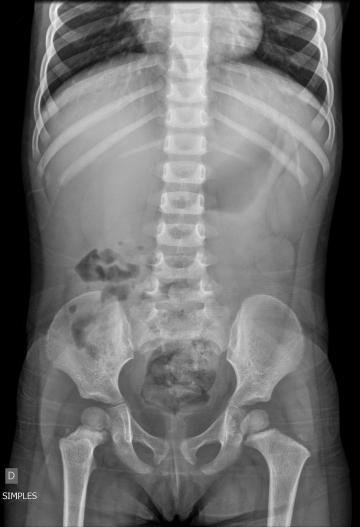

Suspeitando-se da classica dor abdominal causada pela constipação, muitas vézes encontrada no nosso serviço, solicita-se Rx de abdomen simples. Laudo do especialista: Estruturas ósseas íntegras. Distribuição habitual de fezes e gases em alças intestinais. Ausência de imagens cálcicas sugestivas de cálculos renais ou biliares radiopacos (basicamente, Rx normal).

Solicita-se instilação de 2 tubos de Minilax com avaliação da evacuação insatisfatoria. Vinte minutos depois a criança começa com uma nova série de colicas, doloridas, é alojada na sala de tratamentos e infundem-se 0,4 ml Buscopan em bolus e. v. com resposta positiva imediata, solicitando-se uma hemograma e uma coleta urinaria por sonda. Mantida na sala de observação. Resultados: hemograma absolutamente normal, urina negativa para ITU. No entanto, as colicas voltam, e como já tinham passado 2 horas da ultima administração, repita-se a dose de buscopan e. v.. Depois de passar o ultimo episodio álgico, solicita-se uma nova lavagem intestinal, desta vez com Fleet Enema. Com essa segunda lavagem a criança evacua uma amostra de fezes pastosas, com muito muco e de cor discretamente avermelhada, que parece 'geleia de morango'. Passado um intervalo de tempo depois da segunda lavagem, as dores voltam, criança recebe a terceira dose de buscopan e é solicitado US de abdomen. Laudo: ' - Ausência de liquido livre na cavidade abdominal. Bexiga com capacidade normal, paredes finas e regulares e conteúdo homogêneo. Estudo ultrassonográfico dirigido para região abdominal, evidencia-se no presente momento formação em aspecto de 'lesão em alvo', na topografia do hipogástrio, medindo 2,5 x 3.5 cm, com camada externa de 0,8 cm de espessura, sem caracterização de causa secundária pelo método ecográfico.'

Radiografias abdominais simples, em decúbito dorsal e em pé permitem a formular a SUSPEITA de intussuscepção (0,05 pontos), mas não em todos os casos (estima-se uma acuracia de 50%).(0,05 pontos)

DISCUSSÃO: Esclarecemos desde o início que as radiografias têm valor limitado, como ferramenta de triagem, quando achados sugestivos são encontrados. NÃO utilizar na CONFIRMAÇÃO do diagnóstico e NÃO utilizar como um ÚNICO TESTE para o diagnóstico. A ULTRASSONOGRAFIA é a ferramenta de triagem para a grande maioria das instituições.